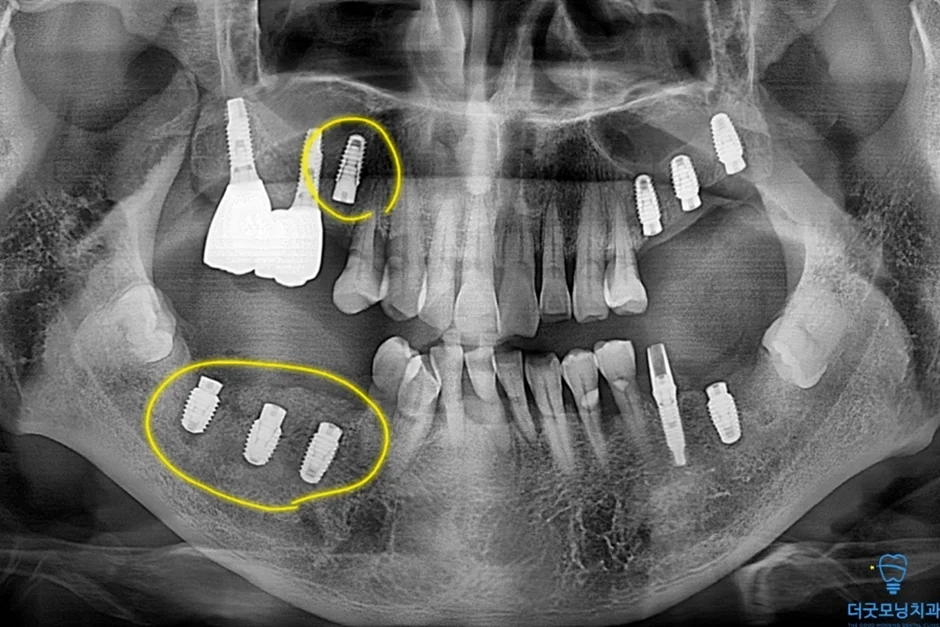

2. 검진 결과 — 파노라마 엑스레이 & CT 분석

먼저 파노라마 엑스레이와 CT를 통해 구강 전체 상태를 확인하였습니다.

■ 왼쪽 위 (상악 좌측)

상악동이 많이 함기화되어 있어 상악동 골이식(치조정 접근 상악동 거상술)이 반드시 필요한 상태였습니다. CT 확인 결과 가용골이 매우 부족한 것이 명확히 확인되었습니다.

■ 오른쪽 위 (상악 우측)

치주염으로 인해 치아가 흔들리는 상태였으며, 발치 후 즉시 임플란트 식립을 계획하였습니다.

■ 아래 양쪽 (하악 좌·우측)

임플란트 주위염이 발생하여 기존 임플란트를 제거하고 재수술이 필요한 상태였습니다. CT 상 신경관까지 어느 정도 거리가 확보되어 재수술은 무리 없이 진행 가능하였습니다.

노란색 표시처럼 임플란트 식립 잘 마쳤습니다.